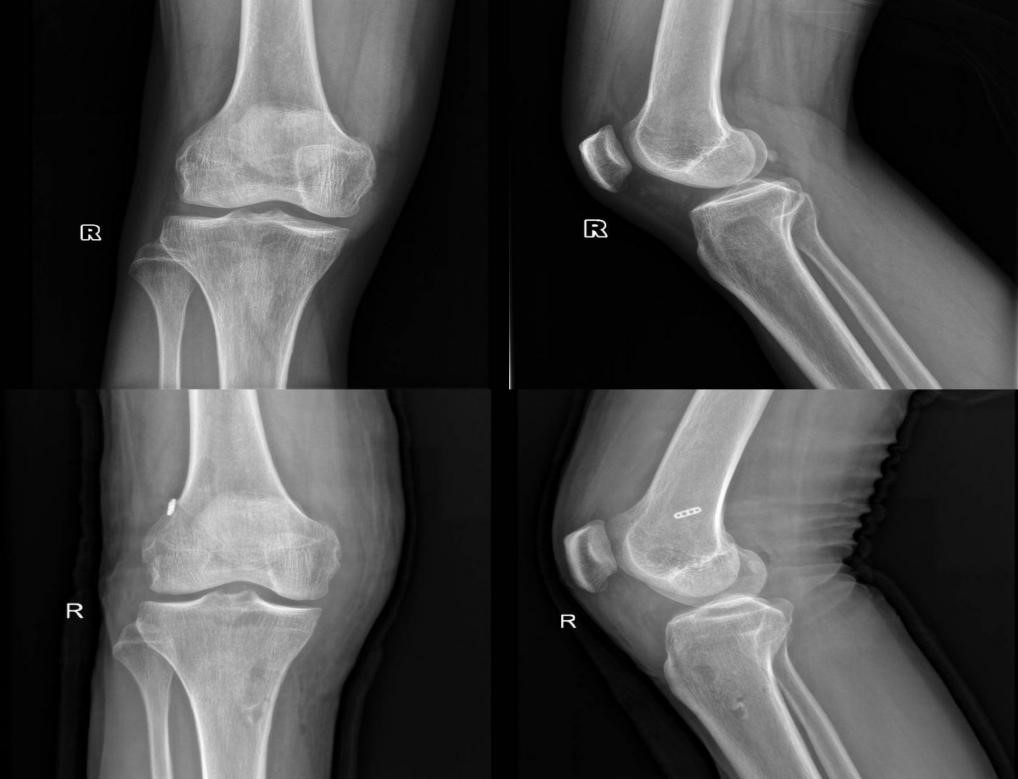

急性前交叉韧带损伤发生时,患者常可听到撕裂声或感到关节异常,随后伴有膝关节剧烈疼痛、活动受限与肿胀。Lachman试验、轴移试验和前抽屉试验这三项检查的敏感度和特异度最佳。MRI是评估前交叉韧带损伤的主要影像学方法。MRI可评估膝关节有无合并半月板损伤、软骨及其他韧带损伤,在急性损伤期用于观察对吻型骨挫伤与骨髓水肿信号等。X线主要用于排除是否合并骨折。